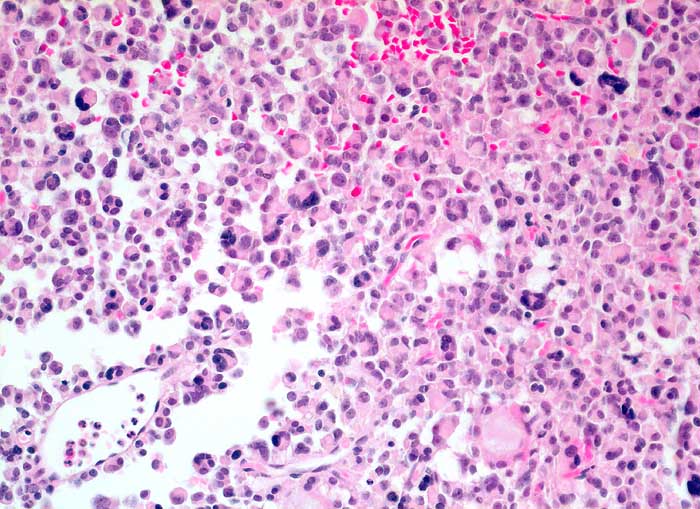

Die Ausstriche sind zellreich und die Zellen sind einzeln, in papillären Verbänden oder Gruppen angeordnet. Zytoplasma ist reichlich vorhanden und ist abhängig vom Typ des Adenoms eosinophil oder basophil. Im Gegensatz zum bunten Zellbild einer normalen Hypophyse wirken die Zellen des Adenoms eher gleichförmig. Die Kerne sind rund und monomorph, das Chromatin ist fein oder Pfeffer und Salz artig. Nukleolen sind meist klein, können aber auch prominent sein. Dignität und funktionelle Eigenschaften sind zytologisch nicht bestimmbar.

Die Differentialdiagnose umfasst Oligodendrogliome und hoch differenzierte Adenokarzinommetastasen.

Unten werden zwei verschiedene Fälle gezeigt.